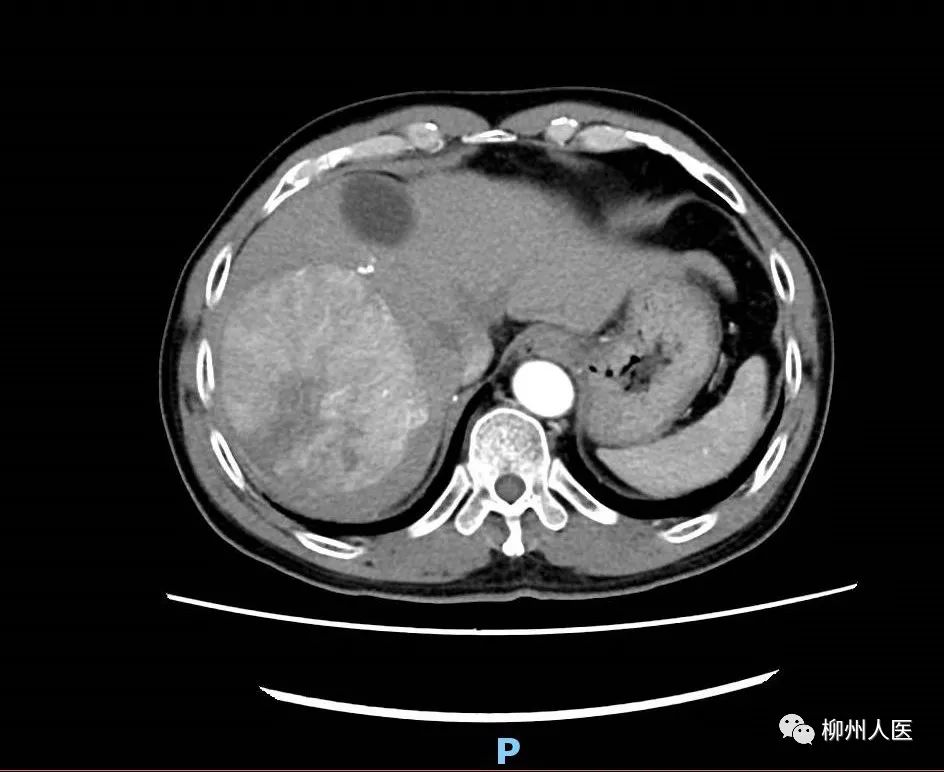

▲第一次手術前

綜合外科肝膽病區團隊組織討論,患者右肝腫瘤巨大,完全切除腫瘤后所剩余的肝臟體積不足標準肝體積的30%,術后極可能出現肝功能衰竭導致死亡。考慮到患者的實際情況,肝癌MDT團隊進行了充分討論。通過數字化影像學肝臟解剖重建、模擬肝切除,計算殘余肝體積和標準肝體積,并對患者進行了全面綜合評估,最終制訂了治療方案——“ALPPS手術(聯合肝臟分割和門靜脈右支結扎的分階段肝切除術)”,簡稱“二步肝切除術”。手術分兩步進行,第一次手術將病側肝臟與正常肝臟分割并對病側肝臟門靜脈支進行結扎,待健側肝臟代償性增大至具備正常所需的肝臟功能后再進行第二次手術,完整切除病側肝臟及腫瘤,讓肝癌患者獲得根治性治療效果。

經過精心的術前準備,綜合外科肝膽病區團隊為患者實施ALPPS第一次手術。術中進行門靜脈右支結扎,同時將左右肝分界線肝實質徹底離斷。術后兩周,CT檢查及肝臟三維重建顯示,患者右側肝體積因低血流量而縮小,左肝外葉體積得到一定程度增長,但因患者肝硬化過重,左肝體積增長較慢,未達到二期肝切除標準。再次MDT討論認為患者體積增加較慢,通過右肝腫瘤TACE(肝動脈化療栓塞)治療控制腫瘤進展。